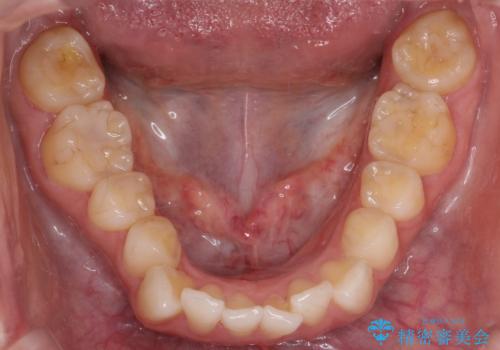

下顎の叢生はIPRを行なって配列しています。

- 前歯の凸凹と口元の突出感を主訴に来院されました。

臼歯関係が上顎前突傾向のため、上の小臼歯を抜歯してワイヤー矯正を行なっております。